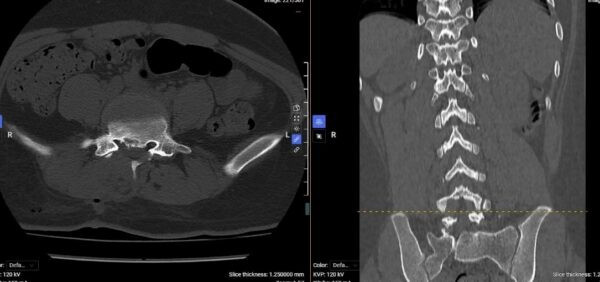

cot-song-tre-3.jpg

Hình ảnh phim chụp CT của người bệnh sau phẫu thuật - Ảnh BVCC